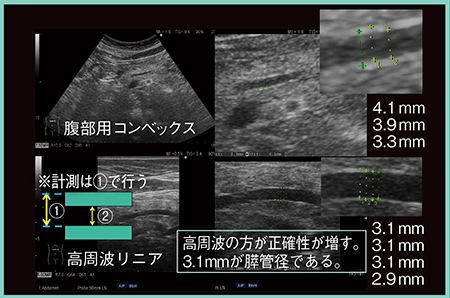

図6に,主膵管の計測のポイントを示す。主膵管の内腔(図6 (2))だけを計測するのではなく,必ず前壁の上から後壁の上まで計測する(図6 (1))。前壁の中央から後壁の中央もしくは前壁の下から後壁の下までの計測でもよいが,前壁の上から後壁の上までが一番計測しやすい。また,高周波プローブを使用することで,計測の正確性が向上する。

計測範囲を図6 (1)とする理由は,パルスの長さが変わっても前後壁の上端同士,あるいは下端同士は平行移動するため,計測距離はまったく影響を受けないからである。

図6 主膵管の計測のポイント